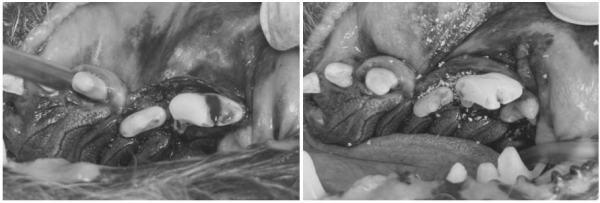

de70cef8385ff32e9ecfc65bf523daeb_1766380596_3926.png

[진행한 치아 치료 과정 GBR/GTR(치조골 재생술)]

치아를 보존할 수 있는 좌측 어금니 부위는

다음과 같은 방식으로 보존 치료를 시행했습니다.

de70cef8385ff32e9ecfc65bf523daeb_1766380606_6386.png

→ 해당 치아의 잇몸을 분리 후,

염증 조직을 제거하고 치은연하 스케일링을 진행한 뒤

de70cef8385ff32e9ecfc65bf523daeb_1766380615_8614.png

뼈 이식재를 해당 부위에 이식하고

차폐막을 삽입한 뒤 안전하게 봉합하였습니다.